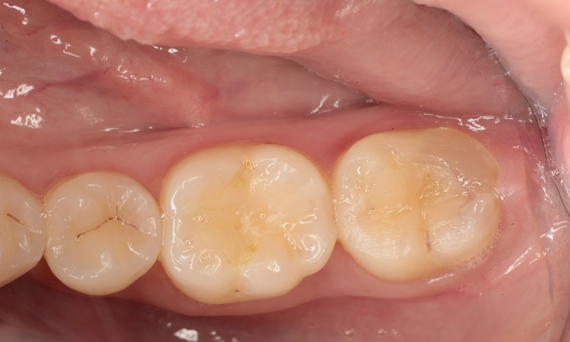

Before: Pre-operative clinical scenario after endodontic therapy.

After: 1 month after the CEREC Tessera onlay was bonded.